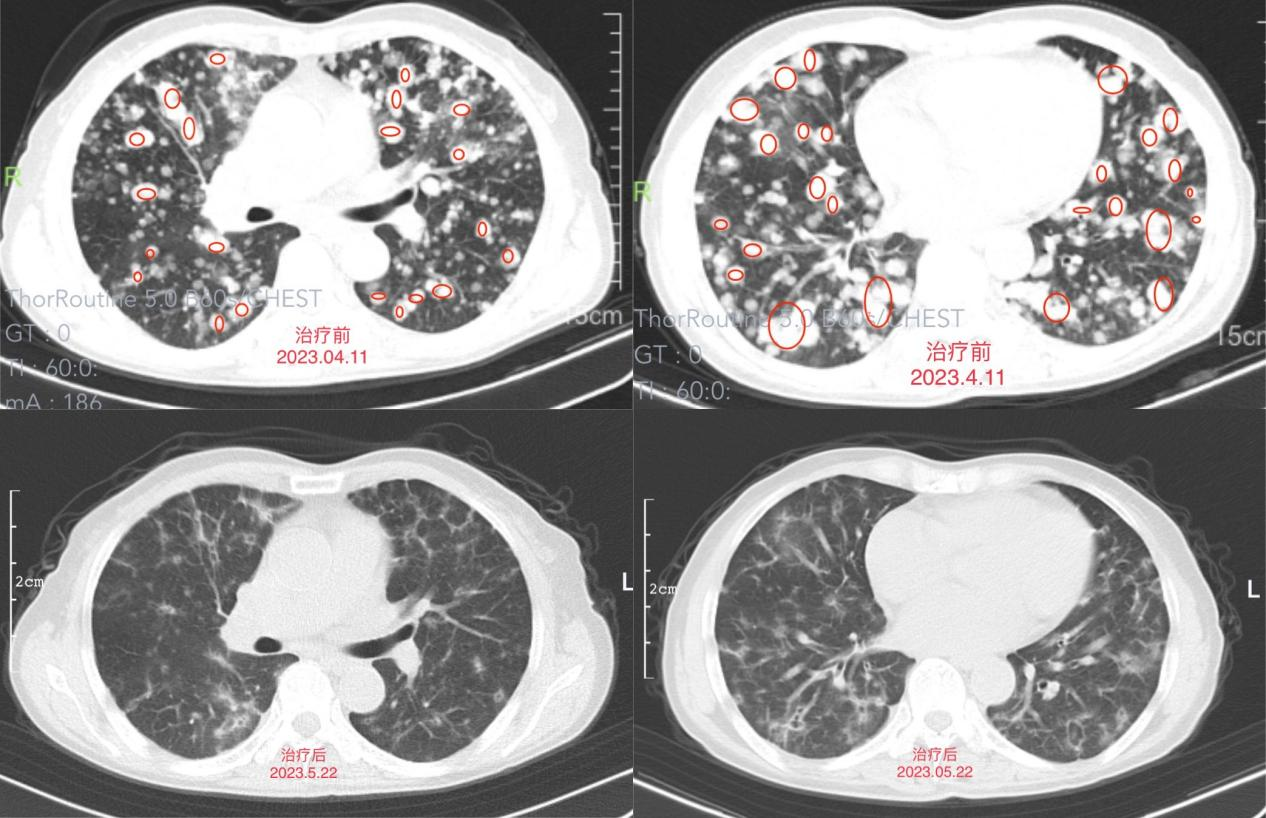

近期,我院肿瘤科收治一位“咳嗽、咳痰,痰中带血1个多月”的患者李阿姨。入院时李阿姨生活不能自理,情绪低落。行辅助检查后诊断为:右肺腺癌 ROS1(+)(IV期)。

肿瘤科副主任、副主任医师王俊组织科室团队讨论治疗方案,结合李阿姨病情及肺癌最新诊疗指南,选择口服分子靶向精准治疗。

经口服靶向药物1个月后李阿姨咳嗽、咳痰及痰中带血等临床症状基本改善,复查胸部CT结果提示肺部病灶及纵隔淋巴结较前缩小,李阿姨的生活质量明显提升。